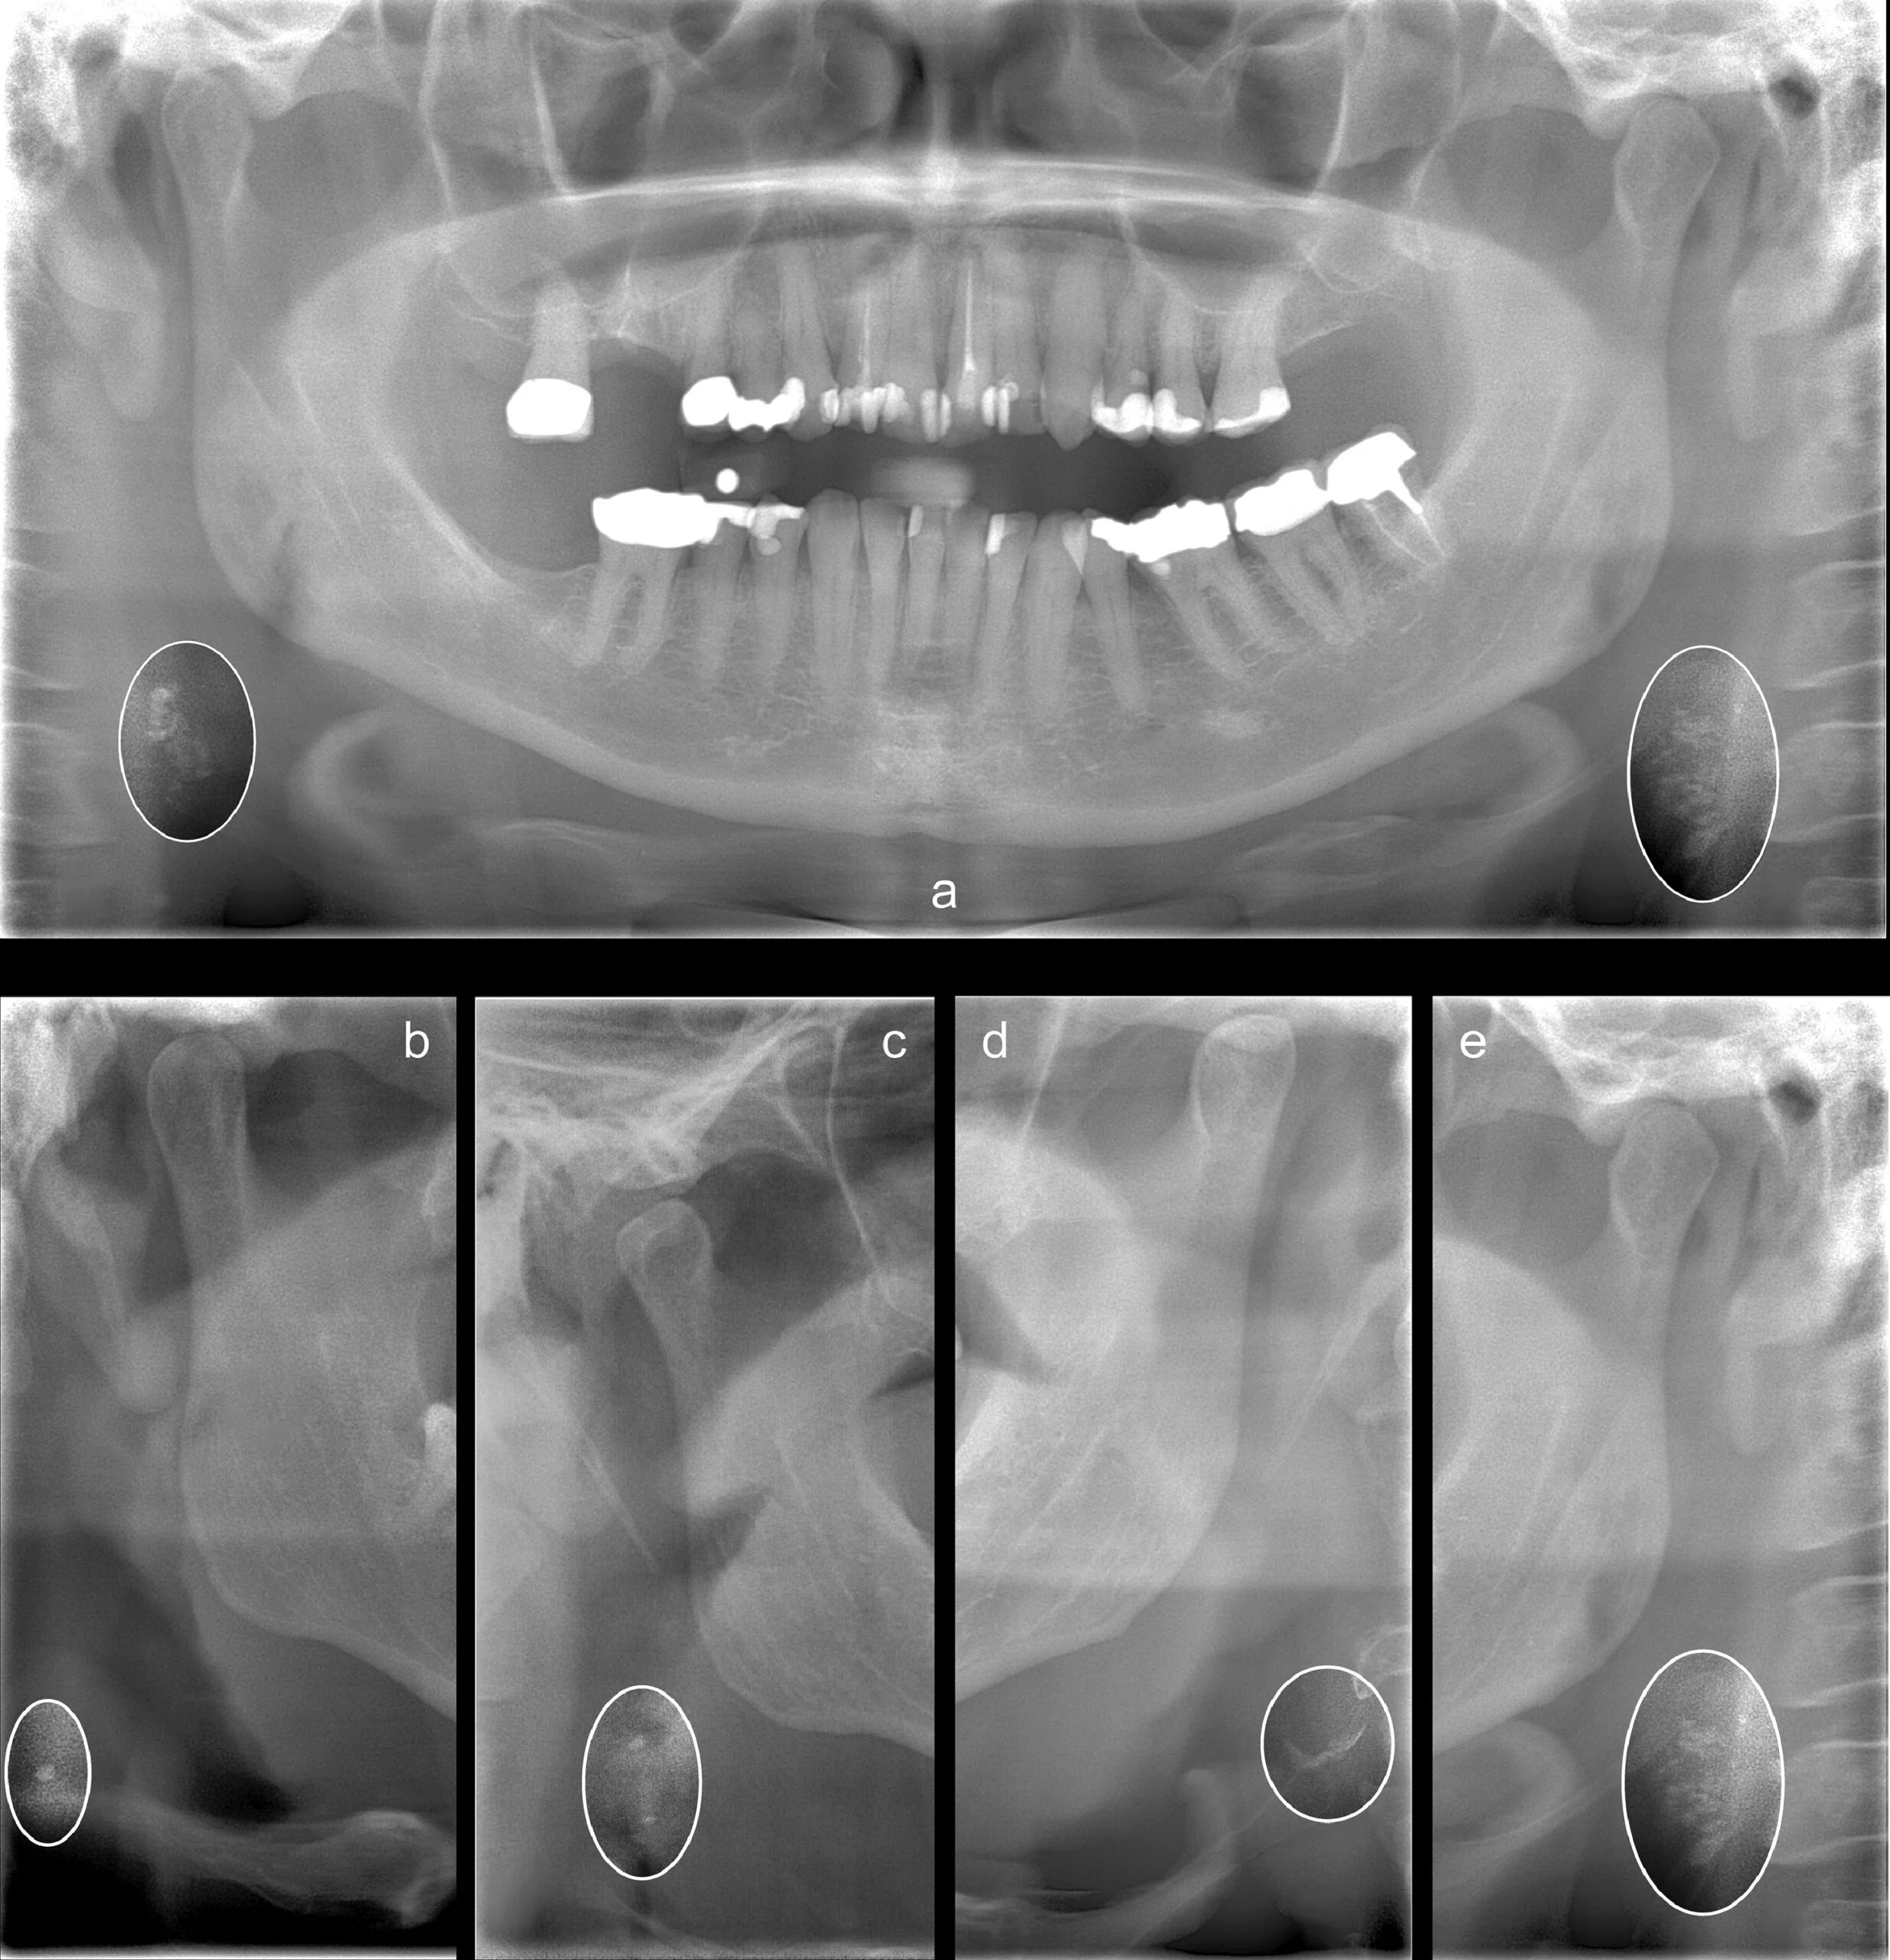

Here are a few sample radiographs from this study:

Dental panoramic radiographs can also show the carotid arteries. When dentists review these radiographs, they might notice radiopaque nodular lesions, which can indicate CAC. According to Friedlander et al. [1], these lesions appear separate from the hyoid bone and are adjacent to the cervical vertebrae, usually between the C3 and C4 vertebrae or below. This is close to the location where the carotid artery bifurcates.

Because all panoramic radiographs are projections, it’s important to be aware that the farther from the focal trough the anatomy is, the more distorted it may appear. In this situation, distortion is not as important because it’s more a matter of flagging the indication. However, if you are using a panoramic x-ray machine that has the ability to capture multiple focal troughs, then it is possible to gather additional views from the single scan. In other words, these panoramic x-ray machines allow the operator to extract more information from the scan by evaluating focal planes that may not be as ideal for the dentition, but more ideal to view the carotid artery.

In some cases, calcifications may not be visible on panoramic radiographs if they are situated below the imaging area. Yet, when CACs are detected, particularly when they are bilateral and outline the vessel, it strongly suggests significant vascular changes that require medical attention [2].